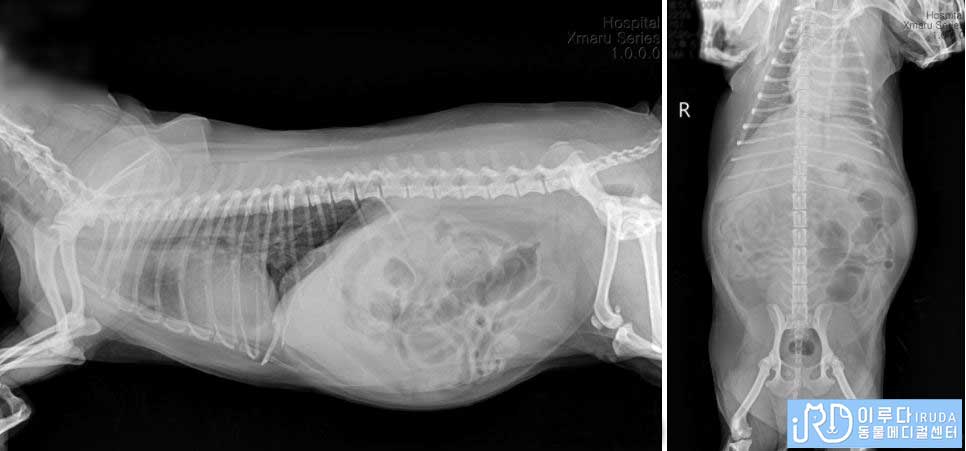

방사선 검사

복부 초음파를 통해 살펴본 결과, 장 내에 있는 다수의 가스가 확인되었습니다. 또한 간, 신장, 방광 등의 장기에는 문제가 없었지만 자궁의 크기가 비대하다는 것을 확인할 수 있었습니다. 방사선 검사와 복부 초음파를 통해 확인한 결과, ㅂㅇ는 자궁 수종과 장염으로 진단되었습니다.